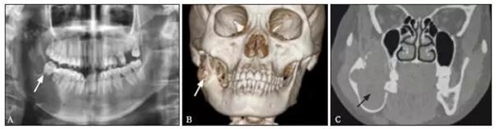

免疫組織化學(xué)結(jié)果:S100彌漫陽(yáng)性、CD21陰性、CD57陰性、CR陽(yáng)性、結(jié)蛋白陰性、鈣調(diào)結(jié)蛋白陰性、ALK陰性、PCK陰性、Ki-67表達(dá)2%~5%陽(yáng)性(圖2)。1.5 隨訪患者術(shù)后切口愈合良好,牙無(wú)松動(dòng),咬合關(guān)系良好。術(shù)后復(fù)查顯示傷口愈合良好,骨斷端生長(zhǎng)良好(圖3)。

圖2 病變組織的組織學(xué)檢查和免疫組織化學(xué)檢查

A:免疫組織化學(xué)染色蘇木精-伊紅×200;

B:免疫組織化學(xué)染色S100陽(yáng)性×200(提示神經(jīng)鞘瘤、惡性黑色素瘤、脂肪肉瘤、軟骨腫瘤或其他);

C:免疫組織化學(xué)染色CR陽(yáng)性×200(提示間質(zhì)細(xì)胞腫瘤或神經(jīng)系統(tǒng)性疾?。?。